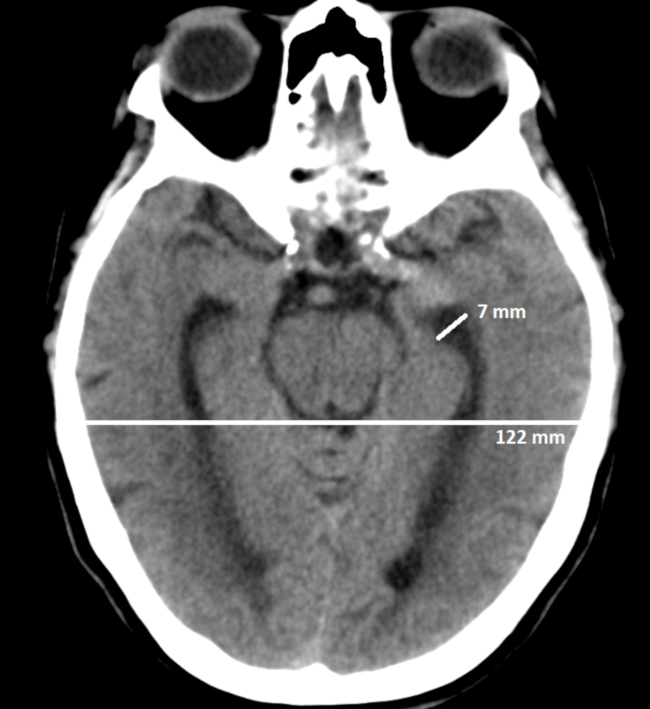

Medición de la línea media

La presencia de una lesión (intra o extra-axial) con efecto de masa, puede generar desplazamiento de la línea media, provocando herniaciones, compresión de cisternas basales, aumento de la presión intracraneal y llevando al óbito.8,9

Este desplazamiento puede mesurarse por TC o resonancia magnética (RM) en cortes axiales, tomando como referencia la posición de las principales estructuras mediales como: septum pellucidum, hoz del cerebro, III ventrículo o glándula pineal.8,9 Para medirlo, se traza una línea recta que pase a través de la hoz cerebral desde su inserción rostral hasta la inserción dorsal en la tabla interna.9,10,11

En caso de que una lesión genere efecto de masa y desplace la línea media, se desplazarán las estructuras mediales anteriormente mencionadas. Para mesurar ese desplazamiento, se traza una línea perpendicular a la línea media hasta donde se encuentra el septum pellucidum o la hoz cerebral y se mide la distancia (►Fig. 2).9,10,11

Un desplazamiento de la línea media mayor a 0,5 cm es un predictor de mal pronóstico para la evolución neurológica de pacientes con traumatismos de cráneo internados en terapia intensiva.12,13